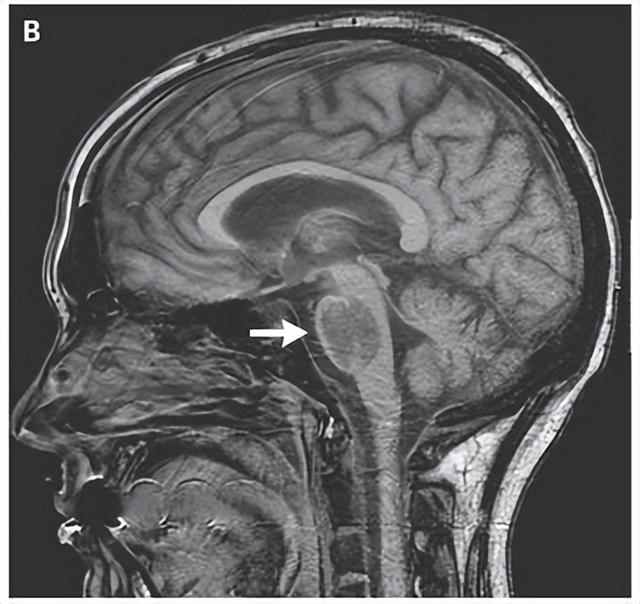

核磁共振成像(MRI)的结果给出了明确答案:接受声音干预的早产儿,在大脑左弓束区域表现出更强的神经连接和更成熟的组织结构。

可能有家长不太清楚左弓束的作用,其实它是大脑中负责语言处理的核心区域之一,就像连接语言理解和表达的“桥梁”,它的发育状况直接影响孩子未来对语言的理解能力、表达流畅度,甚至是学习新知识的效率。

也就是说,妈妈的声音通过每天的规律播放,帮宝宝的大脑提前加固了这道“语言桥梁”,为后续的语言发展打下了更扎实的基础。